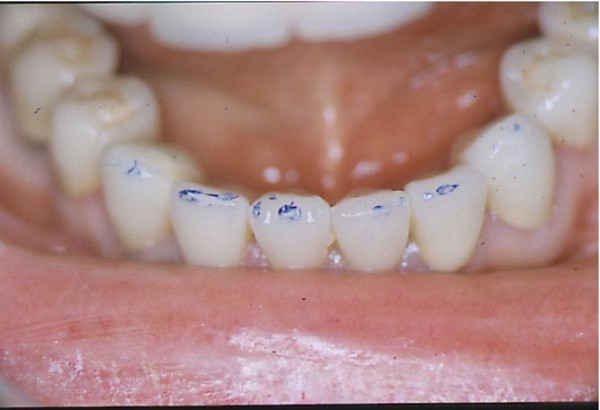

Entidades patológicas como el bruxismo, limitan la terapéutica odontológica y las certezas de un pronóstico favorable y prolongado en el tiempo. El strees, factor predisponente, y alteraciones morfológicas en la oclusión que impiden la disclusión de los sectores posteriores durante las excursiones de la dinámica mandibular, o factores desencadenantes. Caso Clínico Mujer , 53 años, derivado por especialista en Cirugía Máxilo Facial, con evidentes signos de hipertrofia de ambos maseteros. Clínicamente la carencia de las puntas caninas de ambos lados de ambas arcadas, nos habla de ciclos masticatorios eminentemente horizontales, tipo rumiante, donde el fenómeno de DOBLE DESGASTE de las cúspides estampadoras se pone en clara evidencia.(Fig.3 y 4 ) Ambos fenómenos(desgaste exagerado y extrusión dentaria nos habla de una invasión del espacio del maxilar superior, mediante la elevación del inferior, con las lógicas consecuencias musculares por acortamiento: Hipertrofia, acúmulo de ácido láctico, sobrecarga de los elementos tendinosos y capsulares, etc. Se le hace saber al paciente acerca de la necesidad de múltiples técnicas de Rehabilitación ANTES de llegar a reponer sus piezas perdidas. Se le pone en conocimiento de la necesidad de reponer SOLO hasta su primer molar, el que se reemplazará mediante una PREMOLARIZACIÓN, dado que el ancho de su cresta no permite reemplazar un primer molar salvo con riesgos de invadir el ESPACIO BIOLÓGICO necesario para un buen desarrollo de sus funciones. Es necesario tener en cuenta, que la pérdida de dimensión vertical por excesivo desgaste de la porción coronaria es siempre acompañada, por un descenso de las estructuras corticales, desfavoreciendo la relación CORONO/RADICULAR, lo que hace fundamental el ejercicio de unas fuerzas oclusales VERTICALES, a fin de no aumentar la movilidad de las piezas, una vez que la altura adecuada haya sido restablecida, verticalidad que solo se alcanzará mediante la implementación de una GUÍA ANTERIOR adecuada. Se estudia el caso clínicamente y se toman modelos de estudio debidamente montados en articulador semi ajustable en posición de ORC que es la única posición posible para rehabilitar, sin incurrir en alteraciones posicionales de la ATM, ni de elongaciones musculares y tendinosas que generen una nueva situación de strees muscular y empujen al sistema al bruxismo. Se analizan los modelos en forma estática y dinámica, donde se observan no solo las facetas parafuncionales de desgaste sino también la carencia de disclusión canina, patología generadora de dichas facetas, y que, Se confecciona un Encerado de Diagnóstico(Fig.A/B) a partir del cual se tallan las piezas en los modelos y se reproduce un juego completo de provisionales a utilizar durante el procedimiento clínico. (fig. 9) Se realizan las endodoncias y se refuerzan con Pernos Muñones Colados en oro, mediante los conceptos de Alineación Tridimensional correspondientes, instalándose los provisionales efectuados a partir del encerado de diagnóstico, los que cumplen con la tarea de discluir los sectores posteriores , tal como se concibió en dicho encerado.(Fig.10-11-12-13-14) Transcurridos seis meses de control, donde se verifican las funciones del sistema, dentro de un marco adecuado de ortofunción en el cual tal vez el más importante índice es el escaso desgaste de los provisorios, los que funcionan en una adecuada OCLUSIÓN en RELACIÓN CÉNTRICA y DIMENSIÓN VERTICAL ,situación esta apoyada por la presencia nocturna de una férula de Relajación, donde podemos observar y además «escuchar» al enfermo decirnos de su mejoría masticatoria y de la desaparición del «estado de agarrotamiento» que sentía en la boca al despertar, verificando que se siguen produciendo las disclusiones adecuadas en todas las excursiones mandibulares. Realizamos entonces al estudio radiológico adecuado, procediendo a instalar ocho(8) implantes roscados, tres de los cuales son insertados con una ligera elevación de ambas mucosas sinusales intra alveolarmente.(Fig.15-16-17) Transcurridos tres meses más y verificando la correcta cicatrización tomamos impresiones para realizar los abuttments de oro correspondientes, sobre los que instalamos un nuevo juego de provisionales que ya dan carga a los implantes.(Fig.18-19-20-21-22) Ahora estamos en presencia de un Sistema Estomatognático que presenta las características idoneas para funcionar, características estas que observamos permanentemente sobre todo la función de la GUIA ANTERIOR. Recién entonces confeccionamos las Restauraciones Periféricas Totales, las que serán realizadas en Porcelana sobre Oro . Se procede entonces a la confección de los sectores posteriores constituidos en este caso por tres premolares en cada hemiarcada de cada maxilar.(Fig.29-30) Se constatan la Estética, el Ajuste Cavo Superficial, El Espacio Libre Interoclusal, la Dinámica Mandibular,etc.(31-32-33-34-35-36-37-38-39-40) Evidentemente un caso exitoso no muestra las bondades de un método. Sin embargo, la casuística popular acerca de la imposibilidad de ser implantados aquellos pacientes que padecen bruxismo es tan frecuente como realizar en bruxómanos, coronas totales con oclusal metálica a fin de no permitir que las fuerzas de la oclusión destruyan nuestro «trabajo, sin tener en cuenta que no es la dureza del metal quien evita la destrucción…. BIBLIOGRAFÍA: 1-Oclusión y Diagnóstico en Rehabilitación Oral. 2-Disfunción temporo Mandibular y Equilibración Oclusal. 3-Rehabilitacion Bucal. 4-Problemas Oclusales. 5-Oclusión. 6-Oclusión. Conceptos para el Clínico. 7-Disfunción temporo Mandibular. 8-Neurofisiología de la Oclusión. 9-Gnatología.Principios y Conceptos.José dos Santos. 10-Oclusión y Rehabilitación. 11-Procedimientos Clínicos y de Laboratorio de la Oclusión Orgánica.

Ajuste periférico provisional Ajuste periférico provisional

Fig.11 Fig.12

Disclusión Canina Der. Disclusión Canina Izq

Fig.13 Fig.14